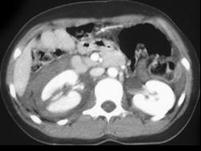

问题 男,32岁,有外伤史,请根据所示图像,选择最可能诊断 ( )

选项 A、右肾挫伤合并右侧肾上腺外伤性出血 B、右肾裂伤合并右侧肾上腺外伤性出血 C、右肾裂伤 D、右侧肾上腺外伤性出血 E、右肾挫伤

答案 B